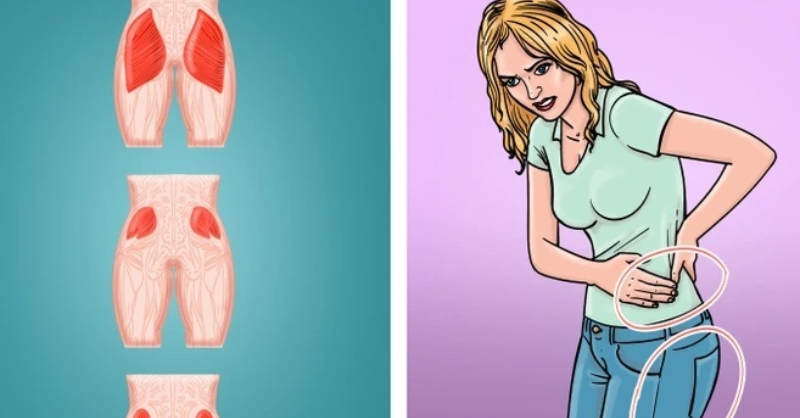

D.e.a.d Butt Syndrome Is Real …Here’s How to Stop It Before It Starts

Dead Butt Syndrome, also referred to as gluteal amnesia, occurs when the gluteus maximus weakens due to prolonged inactivity. This condition is increasingly recognized as a result of...